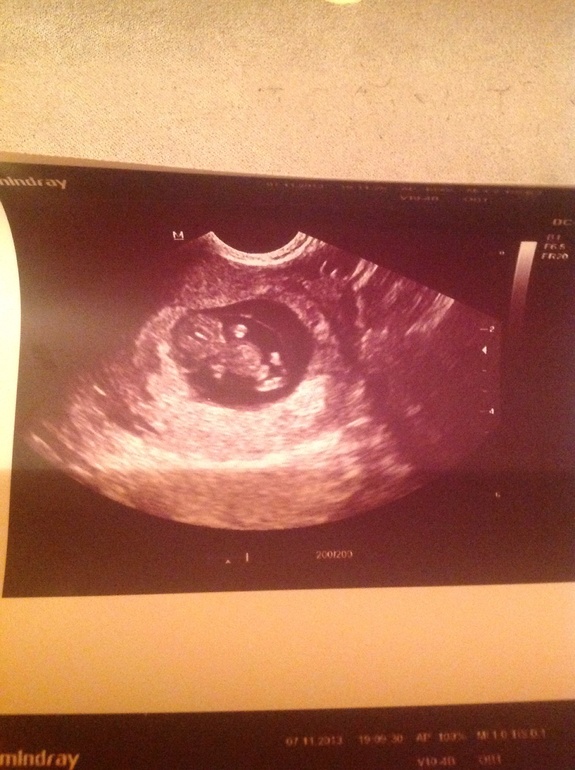

9,5 недель "фотоотчет"

Результаты: УЗИ, КТГ, доплера, скринингаИтак! Сегодня было очередное узи! Отслеживала динамику! Отслойка окончательно пропала!!!! У нас все хорошо наконец-то !!!! Мы уже 2,52 см!!! Сердечко 161 ударов в минуту!!!! А еще вот что нам сказала врач:" вы конечно еще очень маленькие, и 100% сказать не могу. Но кажется между ножек что то болтается!" ))))))) так что теперь жду 19 ноября!!! Первый скрининг!!!! Может там получше видно кто у нас !!!!!

Ух ты какой ракурс хорошии получился, прям видно всего человечка)) кроха такой тьфу тьфу

Да))) вам не много осталось до встречи со своим сокровищем!!!!! Моим тоже не верится ))) 2,5 см а уже и ручки и ножки ))))))